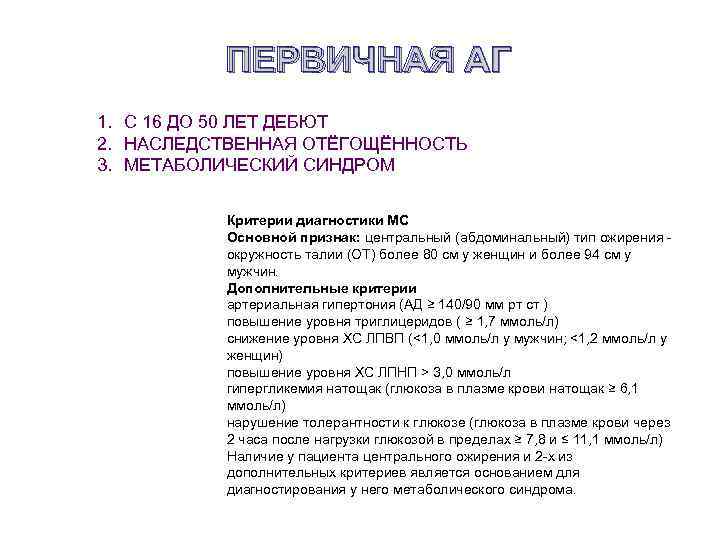

ПЕРВИЧНАЯ АГ 1. С 16 ДО 50 ЛЕТ ДЕБЮТ 2. НАСЛЕДСТВЕННАЯ ОТЁГОЩЁННОСТЬ 3. МЕТАБОЛИЧЕСКИЙ СИНДРОМ Критерии диагностики МС Основной признак: центральный (абдоминальный) тип ожирения - окружность талии (ОТ) более 80 см у женщин и более 94 см у мужчин. Дополнительные критерии артериальная гипертония (АД ≥ 140/90 мм рт ст ) повышение уровня триглицеридов ( ≥ 1, 7 ммоль/л) снижение уровня ХС ЛПВП (<1, 0 ммоль/л у мужчин; <1, 2 ммоль/л у женщин) повышение уровня ХС ЛПНП > 3, 0 ммоль/л гипергликемия натощак (глюкоза в плазме крови натощак ≥ 6, 1 ммоль/л) нарушение толерантности к глюкозе (глюкоза в плазме крови через 2 часа после нагрузки глюкозой в пределах ≥ 7, 8 и ≤ 11, 1 ммоль/л) Наличие у пациента центрального ожирения и 2 -х из дополнительных критериев является основанием для диагностирования у него метаболического синдрома.

ПЕРВИЧНАЯ АГ 1. С 16 ДО 50 ЛЕТ ДЕБЮТ 2. НАСЛЕДСТВЕННАЯ ОТЁГОЩЁННОСТЬ 3. МЕТАБОЛИЧЕСКИЙ СИНДРОМ Критерии диагностики МС Основной признак: центральный (абдоминальный) тип ожирения - окружность талии (ОТ) более 80 см у женщин и более 94 см у мужчин. Дополнительные критерии артериальная гипертония (АД ≥ 140/90 мм рт ст ) повышение уровня триглицеридов ( ≥ 1, 7 ммоль/л) снижение уровня ХС ЛПВП (<1, 0 ммоль/л у мужчин; <1, 2 ммоль/л у женщин) повышение уровня ХС ЛПНП > 3, 0 ммоль/л гипергликемия натощак (глюкоза в плазме крови натощак ≥ 6, 1 ммоль/л) нарушение толерантности к глюкозе (глюкоза в плазме крови через 2 часа после нагрузки глюкозой в пределах ≥ 7, 8 и ≤ 11, 1 ммоль/л) Наличие у пациента центрального ожирения и 2 -х из дополнительных критериев является основанием для диагностирования у него метаболического синдрома.